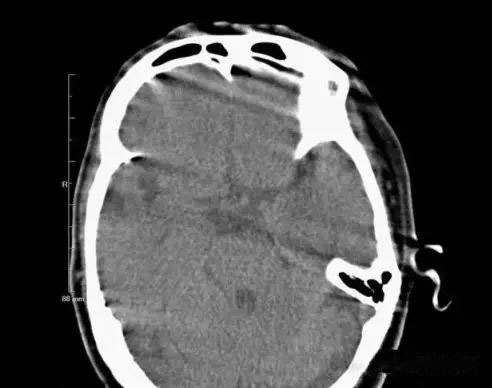

2.異物偽影:主要為密度差別極大的物體如金屬和人體組織一起掃描時所造成,偽影的特點是沿著高密度物體呈放射狀排列。有時圖像上不一定能直接看到目標(biāo)異物,但只要仔細(xì)觀察偽影的放射狀搏列方向,即能找到異物的來源。

2、金屬異物偽影:金屬異物產(chǎn)生的放射狀偽影,嚴(yán)重時明顯影響診斷。在掃描前應(yīng)去除病人體外隨帶的金屬物質(zhì),而病人體內(nèi)無法去除的金屬物質(zhì),如假牙或牙內(nèi)填充物、假肢、各類金屬支架等,可采用傾斜機(jī)架或掃描線的角度盡可能避開。目前也有研究采用某種算法抑制此類偽影。腹部常規(guī)掃描一般服溫開水,盡量不要服含碘造影劑。